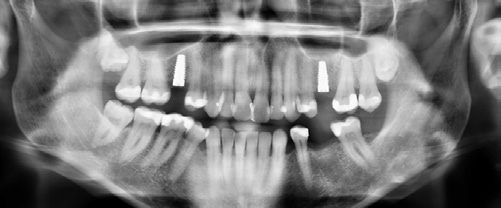

Die Implantate wurden im Anschluss mit einer ausreichenden Primärstabilität von 30 Ncm und einem suprakrestalen Anteil 0,6 mm platziert. Diese suprakrestale Positionierung wird durch einen gegebenenfalls am Profilbohrer anbringbaren Tiefenstopp (Abb. 7) vereinfacht. Für das Einbringen der Implantate steht ein neues, zur „Inter-X“-Innenverbindung formschlüssiges Eindrehinstrument (Abb. 8) zu Verfügung, wodurch eine optimale Kraftübertragung während des Inserierens des Implantats gewährleistet wird (Abb. 9). Die Einheilkappen sind deutlich abgeflacht und ermöglichen einen einfachen primären Wundverschluss (Abb. 10 und 11). Im vorliegenden Fall verlief die Wundheilung komplikationslos. Nach einer auch für Keramikimplantate heute üblichen Einheilungszeit von 3 Monaten zeigten sich die Implantate in der Röntgenkontrollaufnahme stabil osseointegriert (Abb. 12). Es fanden sich an beiden Implantat-Loci entzündungsfreie Weichgewebsverhältnisse, woraufhin mit der prothetischen Versorgung des Implantats begonnen werden konnte.

Die mit dem Abutment verklebten Restaurationen konnten nun entnommen, Zementüberschüsse (Abb. 22) sicher entfernt und die Übergänge von Krone zu Abutment poliert werden. Für die definitive Eingliederung ist der für die Abutmentschraube vorgegebene Anzugstorque von 25 Ncm einzuhalten. Nach erneutem Auffüllen der Schraubenkanäle wiederum mit Teflonband wurden die Zugangskavitäten in ebenfalls üblicher Weise mit Komposit verschlossen. Das Ergebnis sind im vorliegenden Fall 2 metall- und zementfreie, verschraubte und reversible Einzelzahnrestaurationen (Abb. 23). Bei dem routinemäßig durchgeführten Follow-up 6 Monate nach Eingliederung zeigte sich eine an beiden Implantatpositionen reizlose Weichgewebssituation (Abb. 24a und b) und in den radiologischen Kontrollaufnahmen stabile periimplantäre Knochenverhältnisse (Abb. 25a und b).